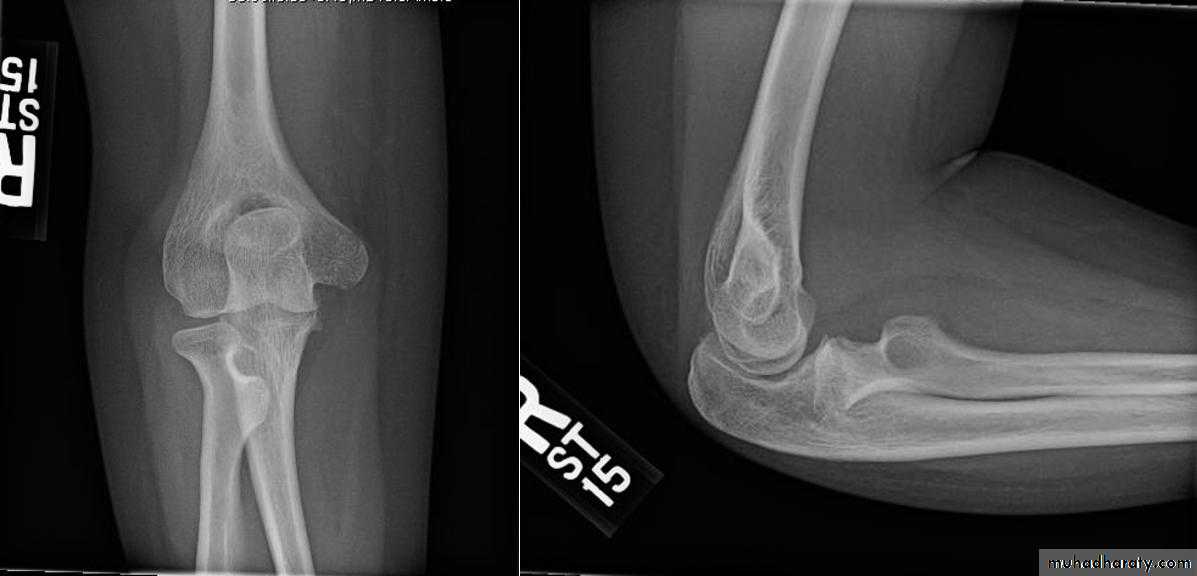

Cubitus varus

Malunion of supracondylar #

Rx : wedge osteotomy of humerus10